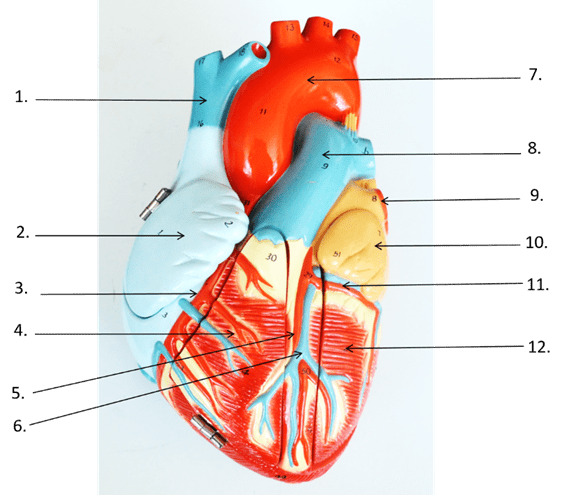

What is the full anatomical name of the vessel labelled "1"

What is the full anatomical name of the vessel labelled "1"

Superior Vena Cava

What is the name of the blood vessel that the arrow labeled number 9 is pointing to?

Pulmonary Trunk

What is the name of the structures that the arrow labeled numbers 3,4, and 5 are pointing to respectively?

3: Tricuspid (right) AV valve

4: Chordae tendineae

5: Right Ventricle

What is the name of the blood vessel that the arrow labeled number 2 is pointing to?

Right Coronary Artery